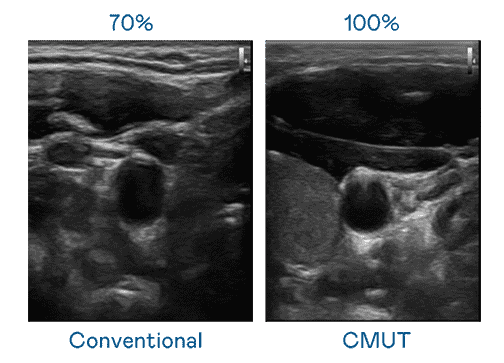

CMUT 技术是一种用电容式微机电元件来产生超音波讯号的技术。。与传统 PZT 压电式技术相比,,,CMUT 频宽增加 30%,,,更宽频的超音波讯号让影像解析度大幅提升,,,,是实现高影像品质医疗超音波扫描、、促进精准医疗发展的关键技术。。。。

超音波影像的解析度高低,,,,首先取决于探头能发出的讯号频宽。。人生就是博 CMUT 可提供高清晰的超音波讯号,,提供高频宽、、、、高灵敏度、、、、影像纹理细节更高的超音波影像,,协助医护人员缩短影像判读时间及利用精准的医疗影像进行诊断。。。。